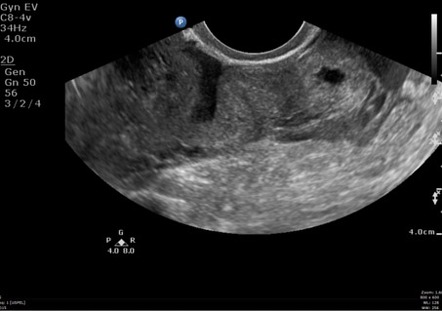

An obsolete term that formerly dignified the finding of a vaginal pulsation that mirrors the maternal heart rate as an early sign of pregnancy. The 12 week scan: transabdominal and transvaginal